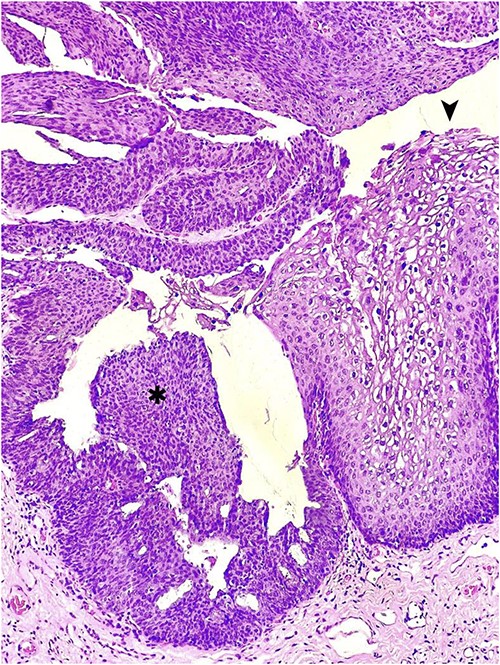

Due to the concern for peri-rectal malignancy in addition to its distressing presentation, the possibility of diagnostic and therapeutic surgical intervention was entertained. The patient was taken to the operating room and, under spinal anesthesia, placed in a jack-knife position. Rectal examination ruled out invasive components. A circumferential, near-total excision was performed, carefully dissecting the tumor off from the sphincter complex. The wound was left open to heal by secondary intention. The pathology revealed multiple foci of high-grade squamous intraepithelial lesion (HSIL/AIN3) arising in a GCA (Fig. 2). HPV testing with immunohistochemistry for P16 was not overexpressed. The patient was discharged with close follow-up and no immediate post-procedural complications.

Hematoxylin and eosin staining of an anorectal GCA, also known as BLT; a hyperplastic papillary exophytic squamous epithelium is appreciated, with prominent fibrovascular cores and koilocytosis (➤) that is confined to the upper third of squamous epithelium on the left.